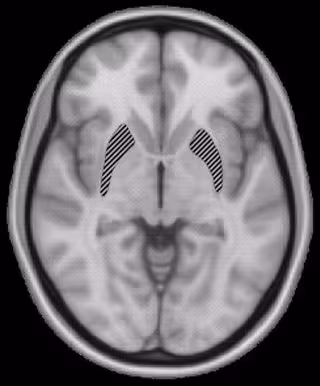

Los investigadores Sheryl Rimrodt y Laurie Cutting, de la Universidad Vanderbilt, en colaboración con la Universidad Johns Hopkins y el Instituto Kennedy Krieger, utilizaron una nueva técnica de resonancia magnética por imagen (MRI) denominada DTI-- para buscar evidencias que vincularan la dislexia con diferencias estructurales en la materia blanca situada en el hemisferio izquierdo del cerebro, donde se aloja el lenguaje.

La materia blanca se compone de fibras que actúan como los cables que permiten la comunicación entre las células cerebrales. La red del lenguaje situada en el hemisferio izquierdo del cerebro está compuesta de manojos de estas fibras y ramificaciones que se extienden desde la parte de atrás del cerebro (donde se incluyen las células de la visión) hasta las partes frontales, responsables de la articulación y el habla.

Los autores del trabajo usaron la técnica de DTI para seguir el curso de un importante bolsa de materia blanca en esta red y descubrieron que recorría la región frontal del cerebro, conocida por estar peor organizada en el cerebro disléxico. También descubrieron que las fibras en esa parte frontal estaban orientadas de forma distinta en el disléxico.